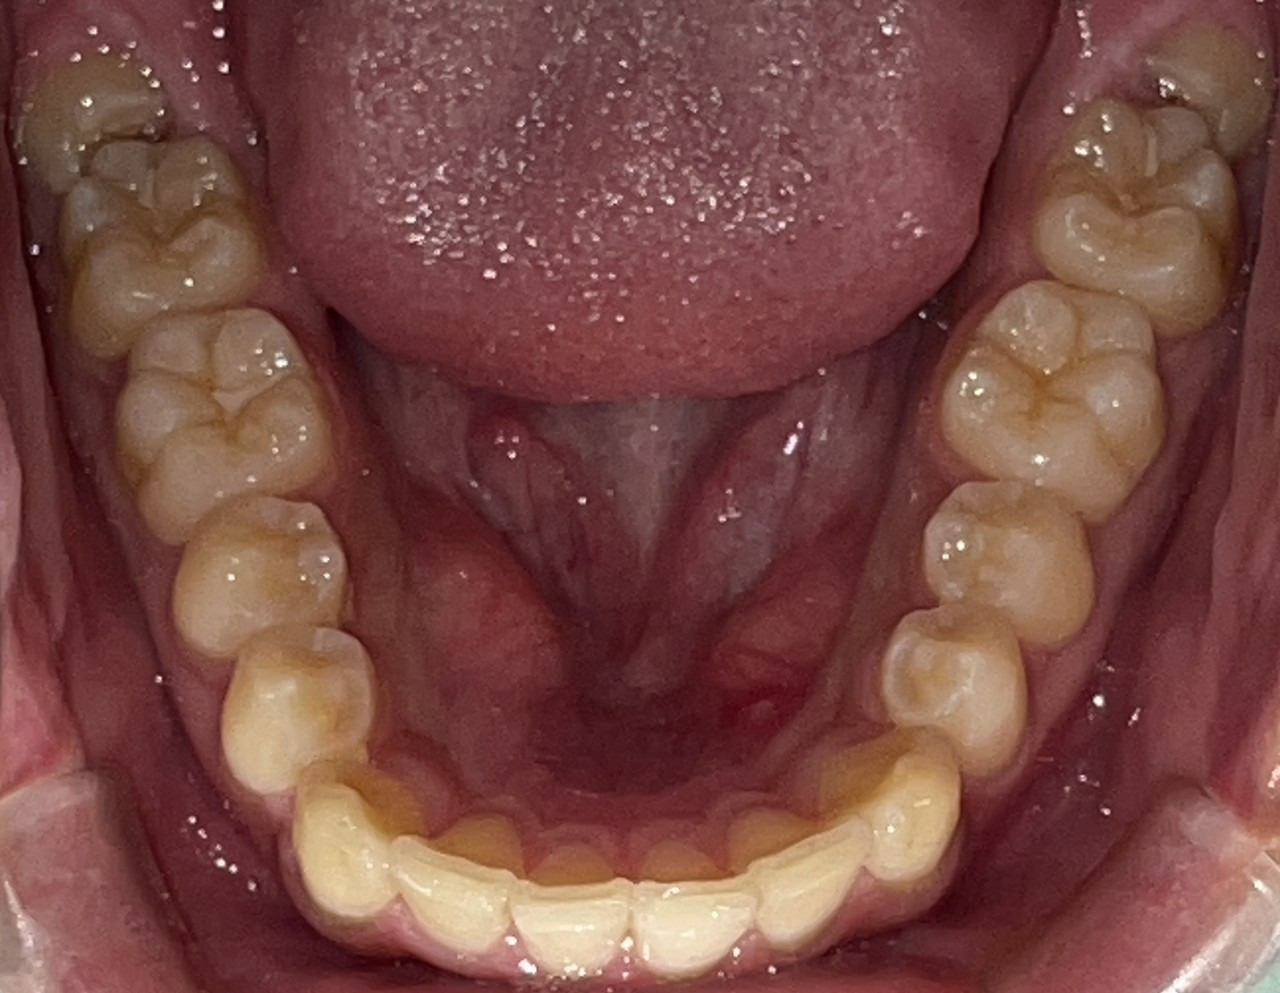

Before

After

矯正の種類 / invisalign GO

年齢・性別 / 40代男性

主訴  /  叢生

治療期間 / 17ヶ月

費用 / 簡易検査 5,000円(税別) 精密検査 30,000円(税別)

両顎マウスピース 450,000円(税別) 両顎リテイナー料 60,000円(税別)

※マウスピース交換時別途調節料5,000円(税別)

副作用 / 口内炎・歯の移動に伴う痛み・知覚過敏 ※数日で収まる場合が多いです

リスク / 後戻り防止の為、夜のみマウスピースで保定を指示